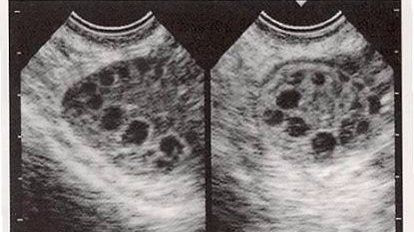

多囊卵巢只是在描述卵巢的变化,它是指:超声提示一侧或是双侧卵巢增大,且出现至少12个直径为2~9mm的无回声区,这就是卵巢多囊了,或者叫做卵巢多囊样改变。

我国多囊卵巢综合征的诊断标准:1、稀发排卵或无排卵;2、高雄激素的临床表现和(或)高雄激素血症;3、卵巢多囊改变:超声提示一侧或是双侧卵巢直径2~9mm的卵泡≥12个,和(或)卵巢体积≥10ml。诊断首先必须符合第1条,其次有第2、第3条之一的,并排除其他高雄激素病因,如先天性肾上腺皮质增生、库欣综合征、分泌雄激素的肿瘤等。